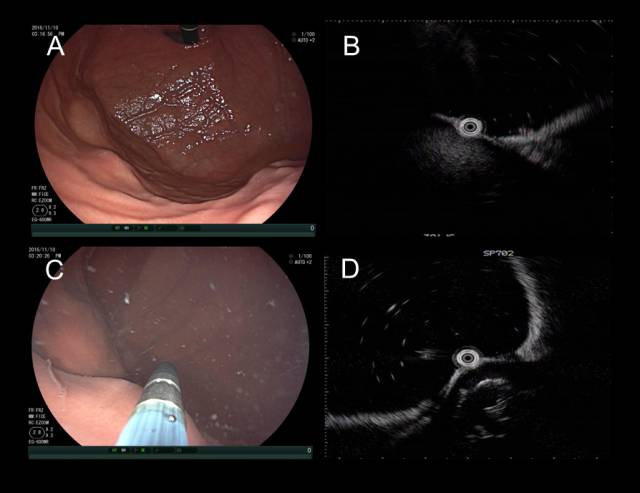

2.肝血管瘤

不同于低回声的囊肿,血管瘤的超声影像通常为中、高回声病灶,上面病例就是一个肝左叶类圆形血管瘤外压导致的胃底隆起。CT等传统影像工具诊断肝脏病灶不难,但部分与胃壁关系密切的外生性血管瘤却是例外。

下面患者在外院胃镜和CT(图 A-B)均考虑胃底粘膜下肿瘤,拟双镜联合切除。

术前来我院完善超声内镜检查提示肝左叶近膈顶血管瘤(图A-B)

图A:环扫EUS提示肝脏近膈顶类圆形血管瘤(白色箭头);图B:线阵EUS见病灶上方的固有肌层完整(白色箭头)